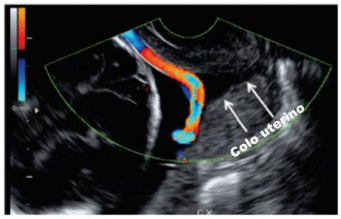

Uma paciente com 24 semanas de gestação realizou ultrassonografia obstétrica com dopplervelocimetria, da qual foi obtida a imagem a seguir.

Assinale a alternativa correspondente a um fator de risco para o diagnóstico da paciente que deu origem à imagem apresentada.